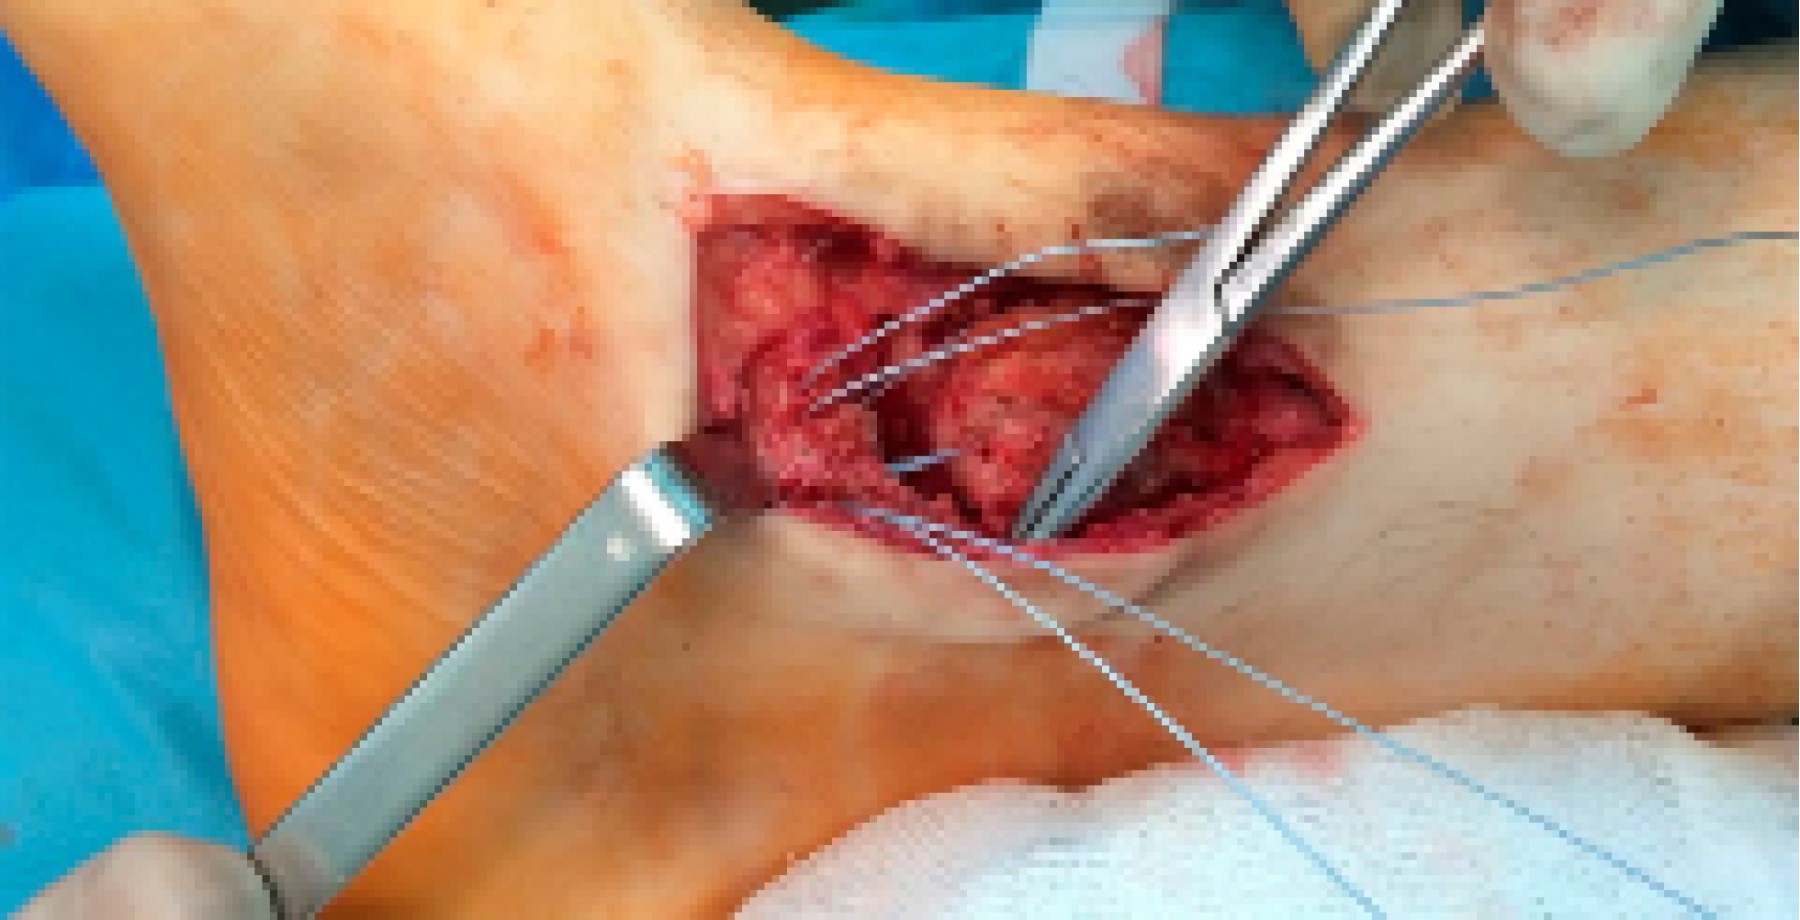

Surgical tecnhique: An antero-medial approach to the ankle joint is made. The deltoid ligament is first detached at its anterior medial malleolus insertion, and the "box resection" is then applied: the articular (lateral) facet of the medial malleolus is removed with an osteotome in vertical alignment. The amount of bone resection should be the necessary for the talus to correctly realign with the tibial plafond. To complete the "box resection", the most lateral 1 or 2 mm of the distal tibial plafond are removed with a small osteotome introduced in a horizontal orientation. A new "shoulder" is created for the talus to get back to its original position. With the talus repositioned, we proceed with correcting the previous malunited syndesmosis. The syndesmosis is reduced with a clamp and fixed with a flexible system, with the ankle in neutral position. An open syndesmosis debridement is required if the fibrous tissue is compromising anatomical reduction.

Through the medial and lateral approaches, under direct visualization, we can confirm the correct tibiotalar congruency, followed by the evaluation of the ankle sagittal motion (plantar flexion and dorsiflexion). To prevent medial instability, the anterior bundles of the deltoid ligament are re-inserted with anchors.

The patient was submitted to hardware removal but the dorsiflexion block persisted. As our goal was to remove the dorsiflexion mechanic block and to restore tibiotalar congruency, we decided to perform the "box resection" (Figure 4 and 5). This allowed an immediate medial talus translation. A syndesmosis debridement and open reduction with a clamp was performed and stabilized with a flexible system (TightRope® Arthrex). We conducted a deltoid ligament re-insertion with anchors (Figure 6). At the end of the procedure, complete dorsiflexion was accomplished with a stable range of motion. Tibiotalar congruency was confirmed in the AP radiograph (Figure 7).